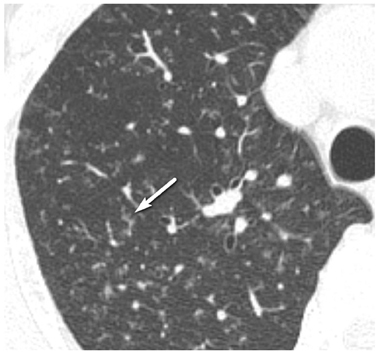

In total, 147 patients who were confirmed with pneumoconiosis on chest radiographs then underwent HRCT; 38 patients with p-nodules on chest radiographs constituted the study population. Chest CT findings, such as the appearance of the p-nodules (ill-defined small nodules, bi-branching structure, well-marginated micronodule, tree-in-bud appearance), the presence of subpleural nodules, changes in the bronchus (e.g., thickening of the bronchial wall, bronchiectasis), and presence of emphysema (centrilobular, perinodular) were reviewed retrospectively by two radiologists in consensus.

In the 38 patients, two did not have nodules, just emphysema. The majority of the p-nodules in the other 36 patients were located in the upper and middle lung fields (n = 33, 91.7%). The most common HRCT findings of p-nodules were ill-defined small nodules, larger than 1.5 mm, and with bi-branching structures (32/36, 88.9%). Well-marginated micronodules were also common (27/36, 75.0%); however, the tree-in-bud appearance was rare (4/36, 11.1%). Changes in the bronchus [thickening of the bronchial wall (27/36, 75.0%), bronchiectasis (19/36, 52.8%)] were identified in 29 patients (80.6%). Centrilobular emphysema and perinodular emphysema were seen in 19 (52.8%) and 9 (25.0%) patients, respectively. All of the patients with perinodular emphysema also had centrilobular emphysema. Subpleural nodules were identified in 17 patients (47.2%).

The distribution of p-nodules was predominantly upper and middle. The most common HRCT findings of p-nodules were ill-defined small nodules and bi-branching structures. Additional useful findings are well-marginated micronodules and changes in the bronchus, such as thickening of the bronchial wall and bronchiectasis.